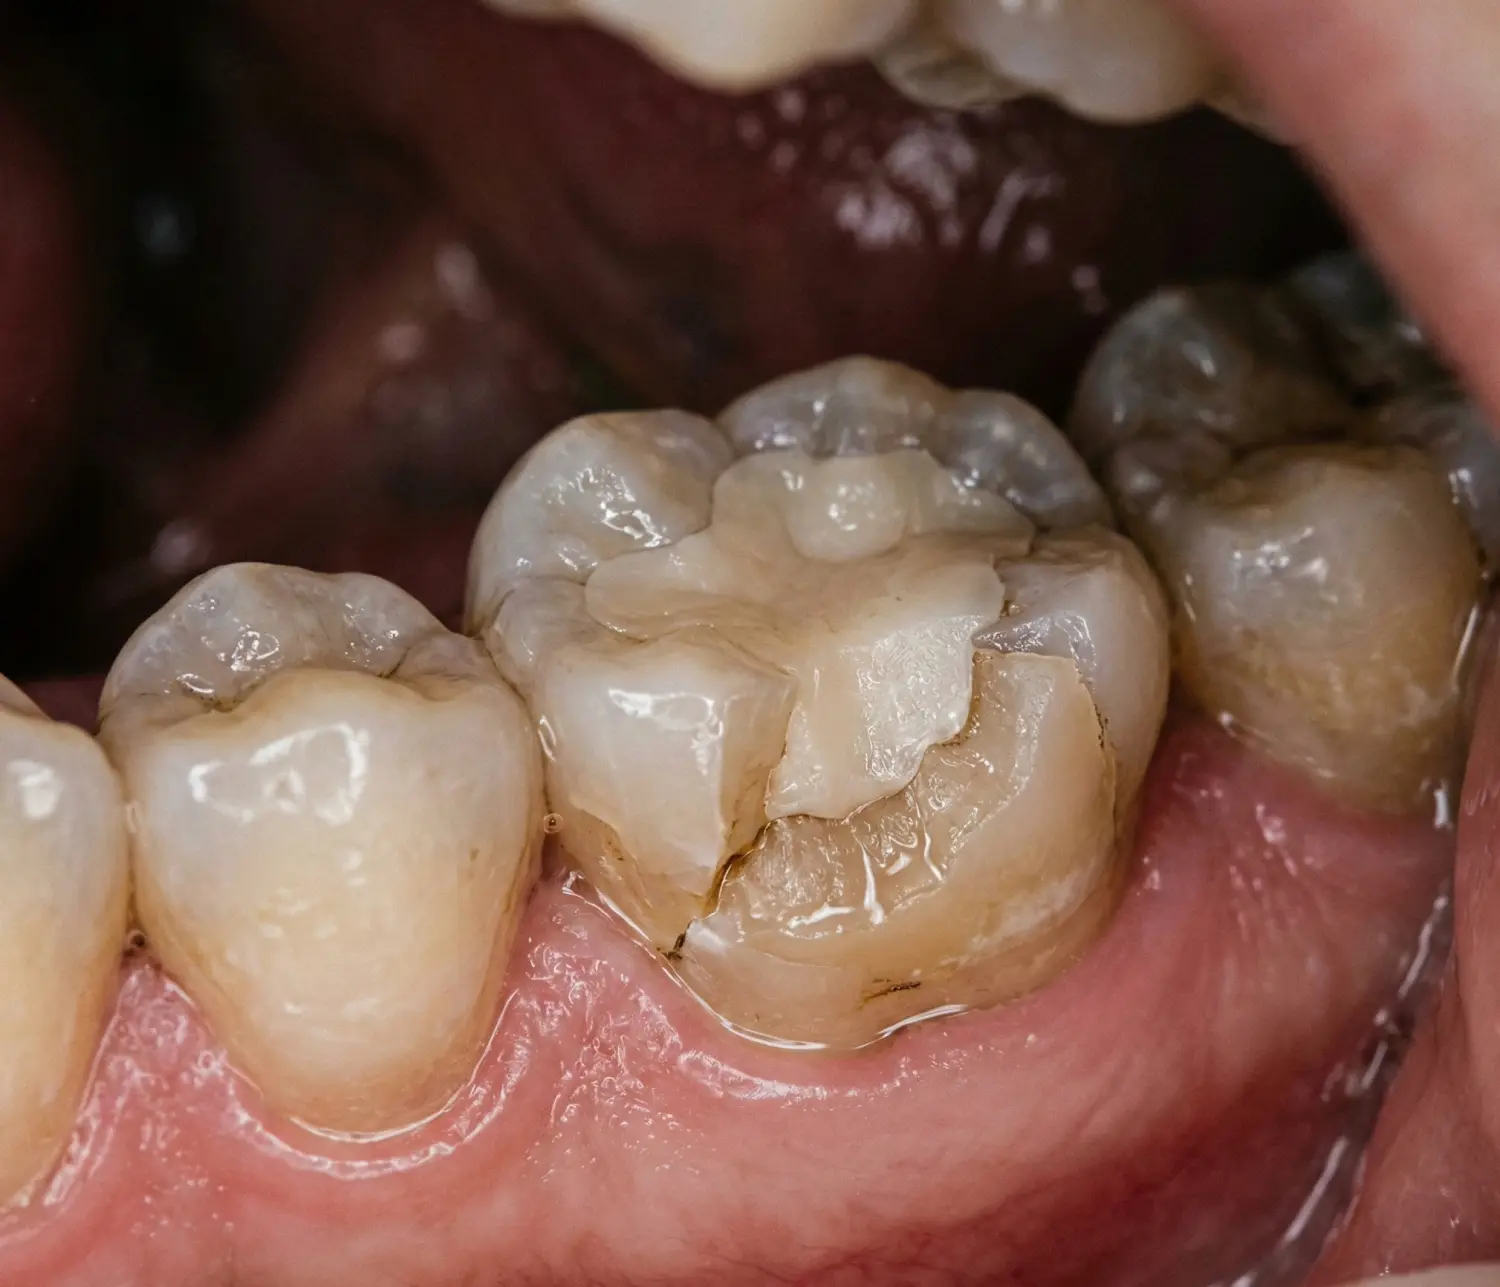

Dolgu Kenarı Kırılan Dişte Tedavi Seçenekleri

Tedavi; kırığın derinliğine ve dişin genel durumuna göre belirlenir. Dolgu olan dişin kenarı kırıldığında en sık başvurulan yöntemler şunlardır:

1. Dolgunun Yenilenmesi

Küçük kırıklarda eski dolgu uzaklaştırılarak kompozit veya seramik dolgu uygulanır. Hızlı ve ekonomik bir çözümdür.

2. İnlay / Onlay Uygulaması

Orta büyüklükteki kırıklarda, laboratuvarda özel hazırlanan inlay veya onlay restorasyonları uygulanır.